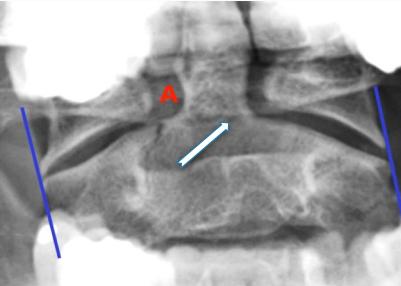

Open-Mouth View

- For C1 and C2

- Odontoid fractures

- Lateral mass fractures

- Look for:

- Symmetry

- Continuity of bone

Fractures of C2-Odontoid

- Identified easily by:

- Open mouth view

- CT scan